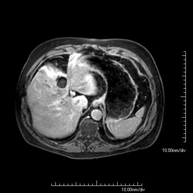

- RM Hígado

Prueba diagnóstica no invasiva que consiste en la obtención de imágenes de alta definición anatómica del hígado mediante el empleo de un campo electromagnético y ondas de radio (con un emisor y un receptor). No utiliza radiación ionizante. Se realiza para estudiar cualquier lesión localizada en el hígado, y también para valorar enfermedades inflamatorias y de depósito. Normalmente se requiere el uso de contraste paramagnético (Gadolinio) para caracterizar las lesiones. Es necesario realizar la prueba en ayunas (6 horas).